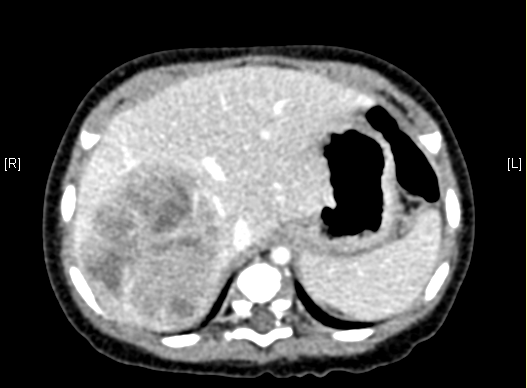

上腹部增强CT:肝右叶巨大占位,肝母细胞瘤可考虑。

术前CT检查:

平衡期